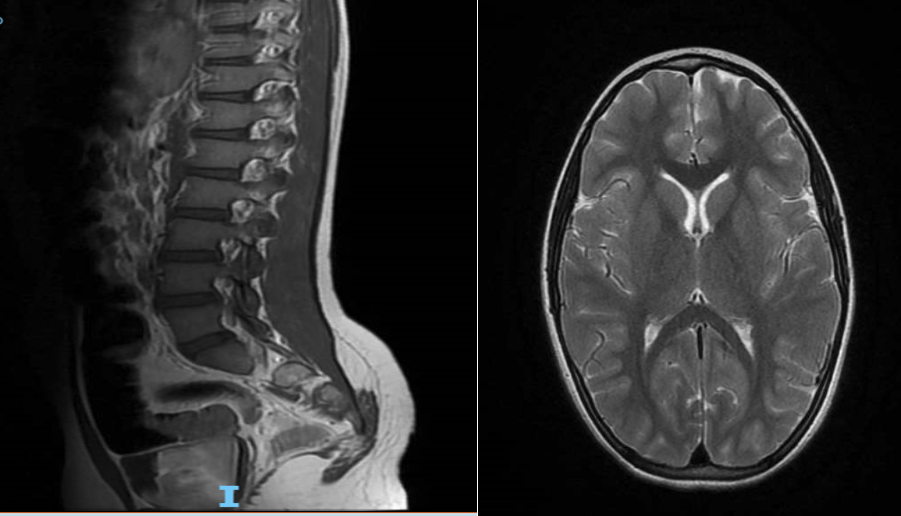

Eseguiamo subito una RM midollo-encefalo (Figura) che mostrerà un modesto coinvolgimento infiammatorio delle leptomeningi, un’intensa impregnazione contrastografica delle radici nervose della cauda equina e una iperintensità degli spazi subaracnoidei. È stata eseguita rachicentesi, che ha mostrato un liquor limpido con la nota dissociazione albumino-citologica (rapporto LCR-albumina / S-albumina pari a 10,67; v.n. 0-5) e assenza di reazione oligoclonale. Gli esami ematochimici mostravano una leucocitosi neutrofila con lieve rialzo degli indici di flogosi; BioFire® respiratorio positivo per rhinovirus ed enterovirus e IgG VCN EBV positive.

Non facciamo in tempo a rallegrarci per la conferma del nostro sospetto clinico di Gullain-Barré, che la piccola presenta un rapidissimo peggioramento delle condizioni cliniche, con disfonia e tachidispnea. Immediata l’infusione di immunoglobuline endovena e altrettanto rapida l’intubazione orotracheale e il trasferimento in Rianimazione Pediatrica, dove resterà per lungo tempo. Il riscontro, già alla RM e all’indagine del liquor, di dati che generalmente all’esordio di malattia sono assenti e il progressivo rapido peggioramento, sottolineano che le manifestazioni cliniche verosimilmente non erano di recente comparsa, come riferito anamnesticamente.